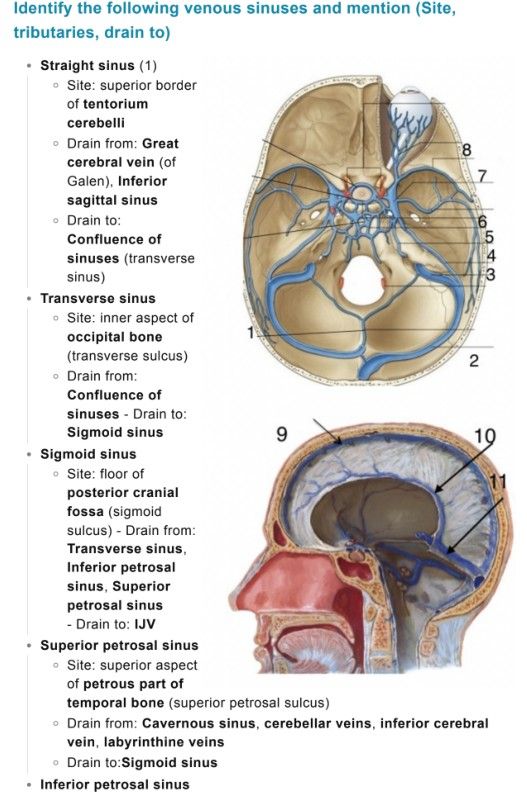

Superior sagittal sinus

Inferior sagittal sinus

Straight sinus

Transverse sinuses

Sigmoid sinuses

Cavernous sinuses

Superior sagittal sinus: runs in falx cerebri → drains to confluence of sinuses (1)

Inferior sagittal sinus: joins great cerebral vein → forms straight sinus (1)

Straight sinus: drains to confluence (1)

Transverse sinuses: from confluence → become sigmoid sinuses (1)

Sigmoid sinuses: drain into internal jugular vein (1)

Cavernous sinus: drains via superior & inferior petrosal sinuses (1)- Cavernous Sinus Detail (3 marks)

Confluence of sinuses = meeting point (superior sagittal, straight, occipital)